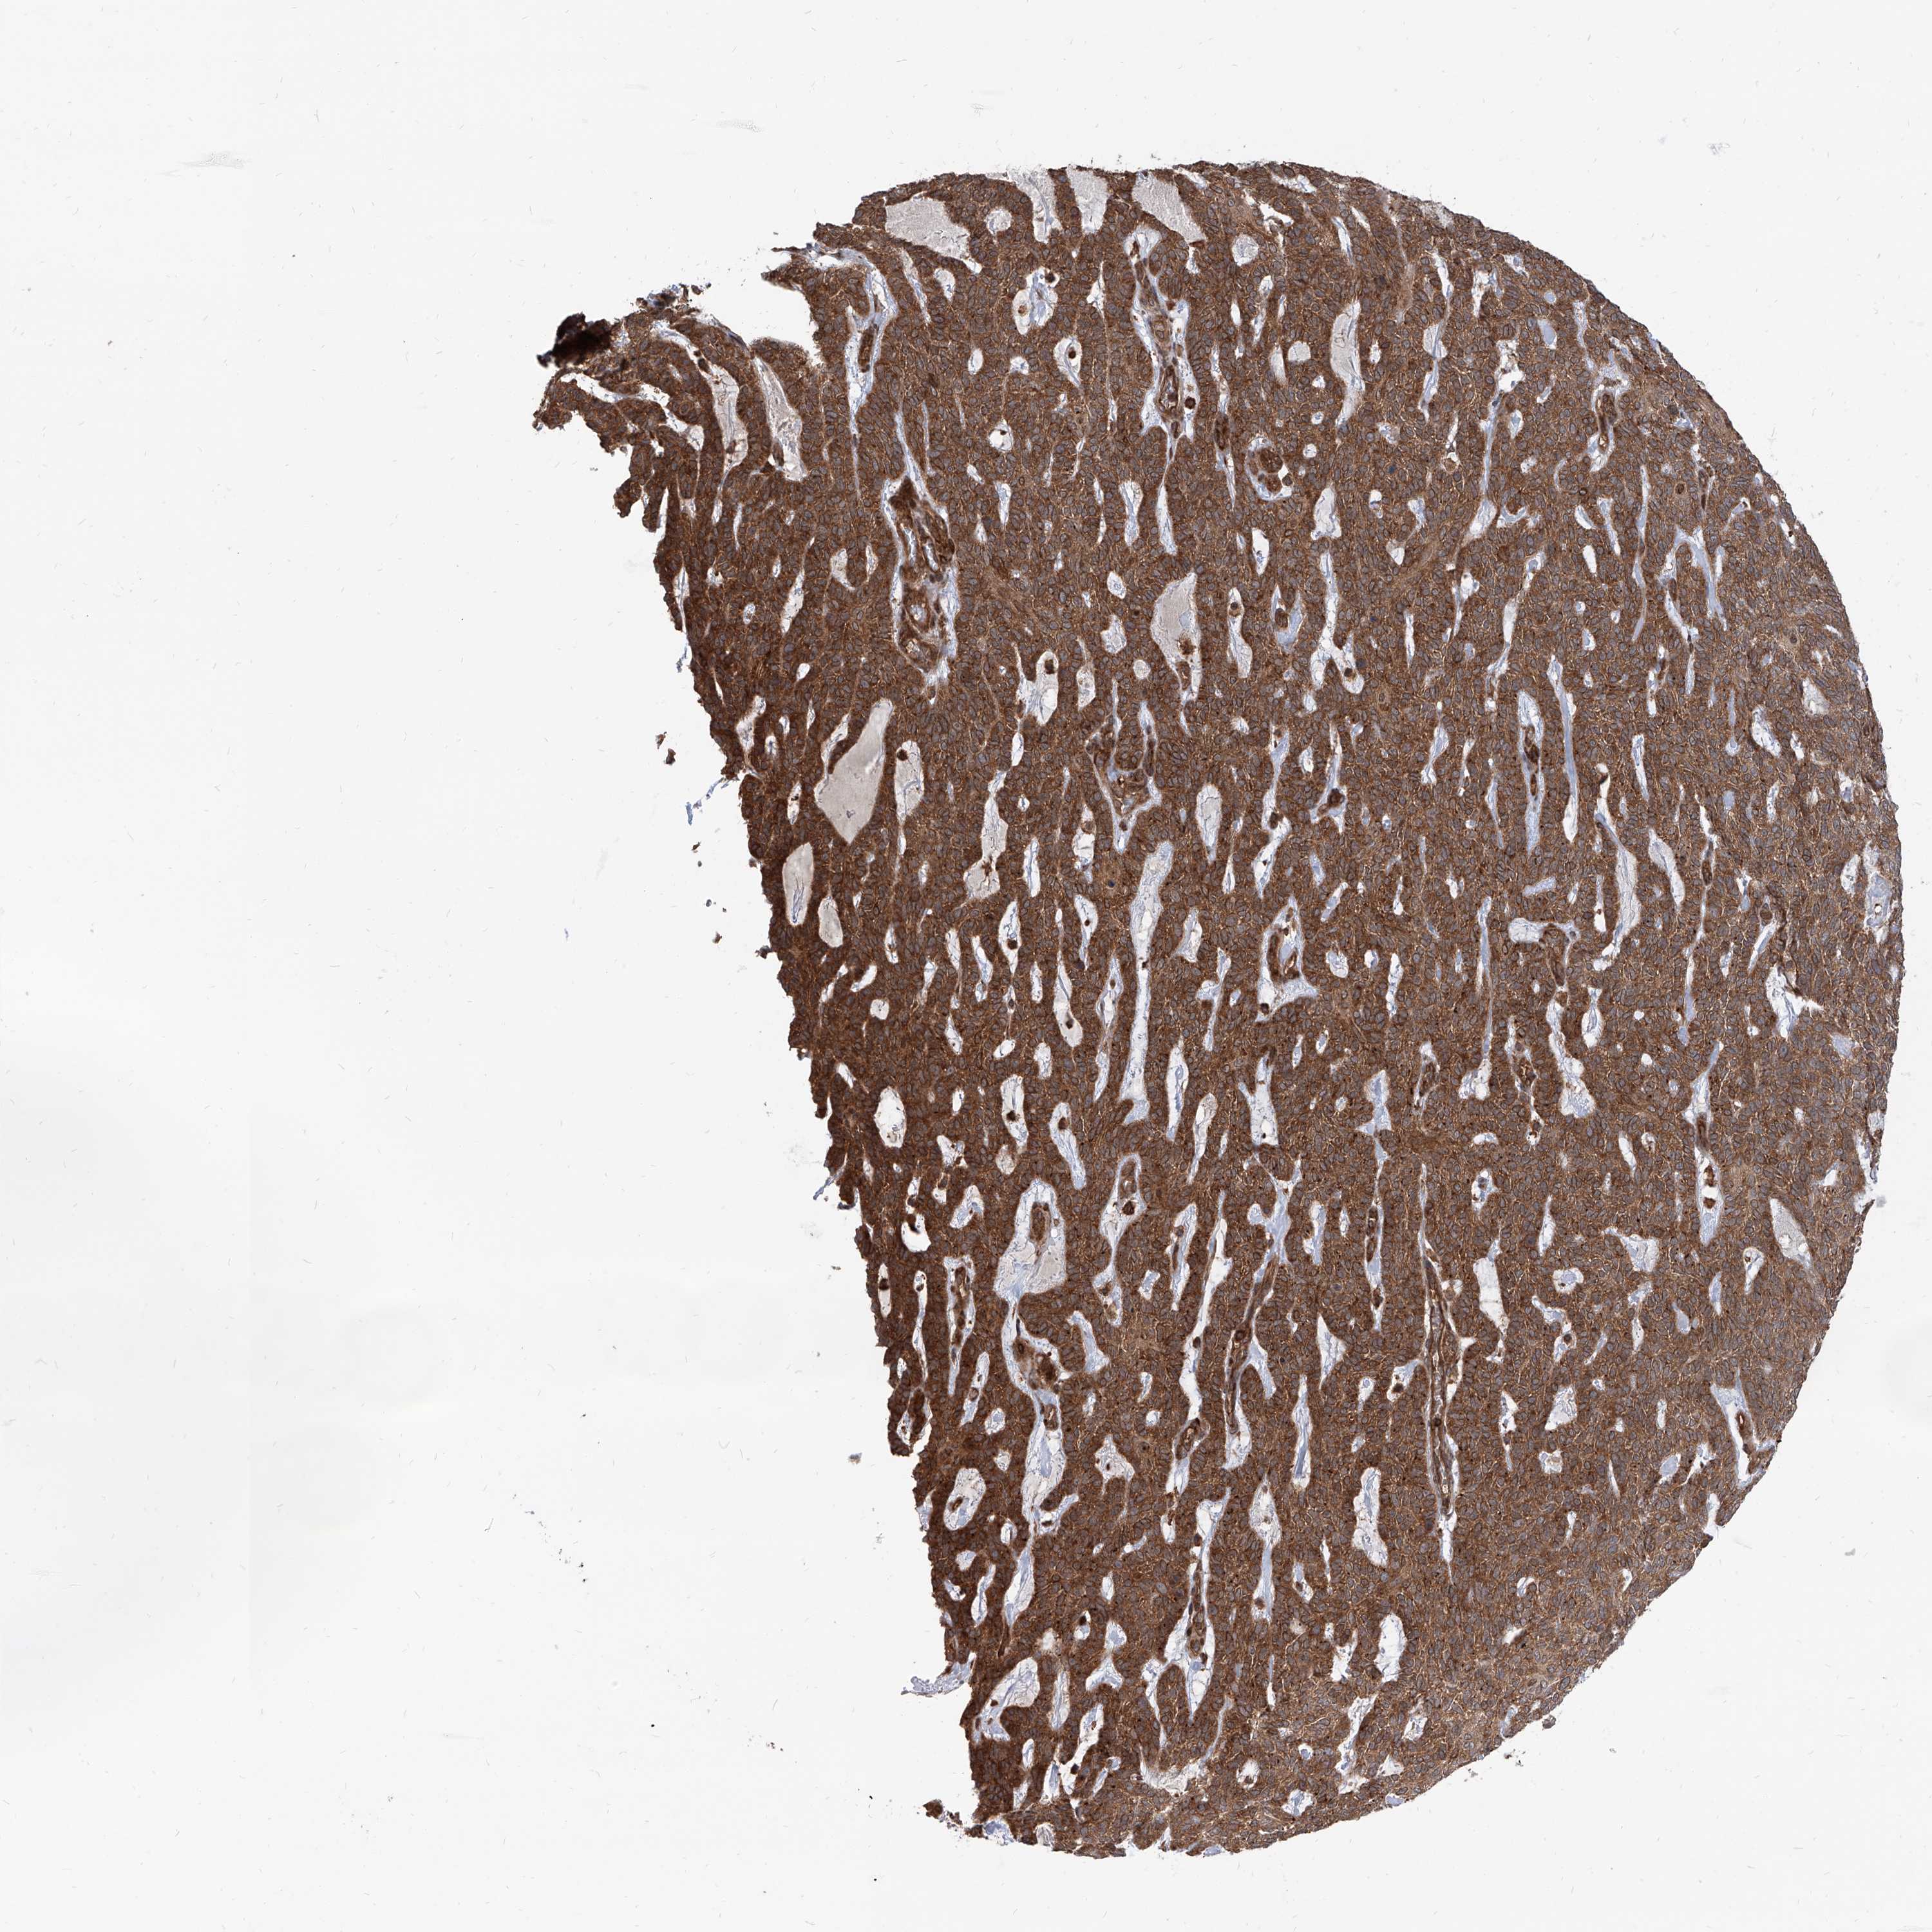

SKIN CANCER - Protein expressioni

A mouse-over function shows sample information and annotation data. Click on an image to view it in a full screen mode. Samples can be filtered based on level of antibody staining by selecting one or several of the following categories: high, medium, low and not detected. The assay and annotation is described here.

Antibody staining in the annotated cell types in the current human tissue is reported as not detected, low, medium, or high, based on conventional immunohistochemistry profiling in selected tissues. This score is based on the combination of the staining intensity and fraction of stained cells.

Each image is clickable and will lead to virtual microscopy that enables deeper exploration of all samples and also displays staining intensity scores, fraction scores and subcellular localization as well as patient and tissue information for each sample.

Antibody HPA031572

Antibody HPA031573